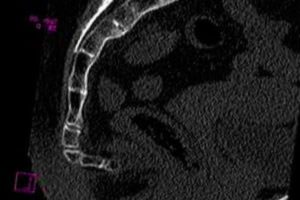

Диагностика осуществляется на основании сбора анамнеза, ручного обследования на предмет установления месторасположения и варианта смещения. Затем может потребоваться рентгенографический снимок органов таза, пояснично-крестцового отдела в нескольких проекциях, компьютерная и магнитно-резонансная томография.

Если же от рентгена не будут получены детали и данные в должном объеме, приходится осуществлять компьютерную томографию. Беременным женщинам лучше заменить ее магниторезонансной томографией.

К радиологической диагностике загиба копчика относится рентгенологическое исследование, которое проводится в разных проекциях, в положении сидя и стоя. Если этот метод не дает полностью раскрыть клиническую картину, пациент направляется на компьютерную томографию.

- рентгенография в нескольких проекциях;

- магнитно-резонансная или компьютерная томография;

- пальпация копчика посредством пальцевого ректального исследования;

- ультразвуковое исследование тазовой области.

Для этого используют рентгенографию, УЗИ брюшной и тазовой полости, компьютерную или магнитно-резонансную томографию позвоночника. После получения всех необходимых результатов начинается само лечение.